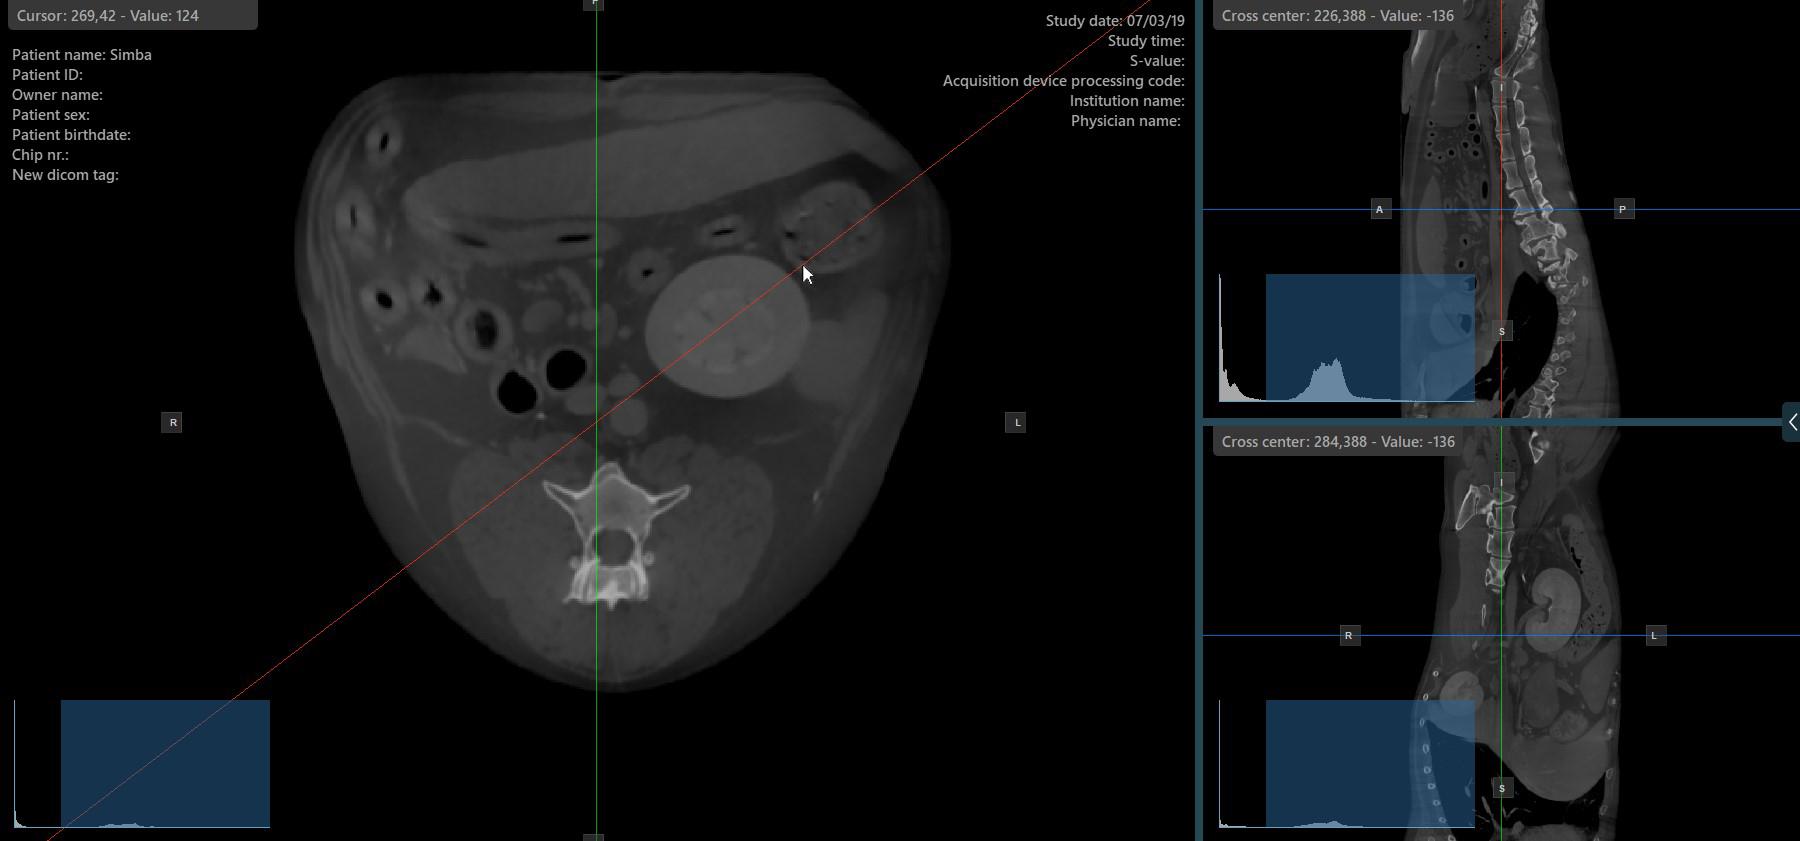

Change Slicer Rotation¶

Altering the rotation of a slicer will change the orientation of the corresponding image planes. Individual slicers can be selected by using the Select Item (Default)

tool, assigned to the right mouse button by default.

Once the specific slicer is selected, drag the slicer in the desired direction to rotate it. The corresponding image plane’s orientation changes accordingly.

By default, each slicer can be rotated separately. The corresponding icon in the left toolbar of the CT Viewer will be deselected when the slicers are rotated individually.